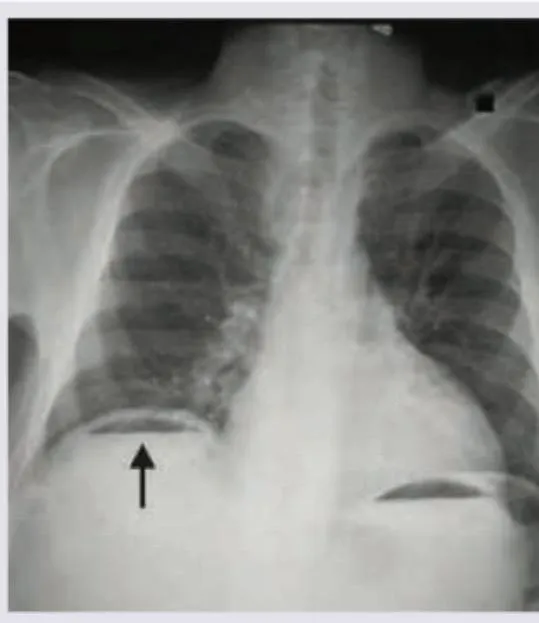

- Perforation: Air under diaphragm on erect CXR (70-80% sensitivity)

- Imaging: Erect CXR (perforation), AXR (obstruction), USS (biliary/gynae)

| Perforated viscus | Sudden onset, board-like rigidity, peritonism | Erect CXR (free gas), CT if unclear | Immediate surgery |

✓ Erect CXR detects 70-80% of perforations; if clinical suspicion high but CXR negative, proceed to CT with oral contrast